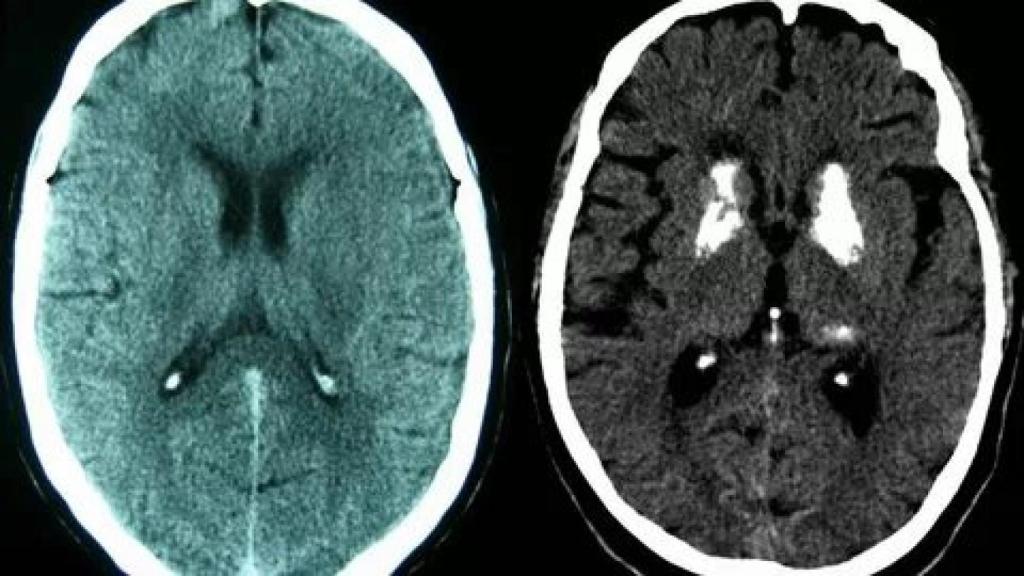

Un escáner cerebral.